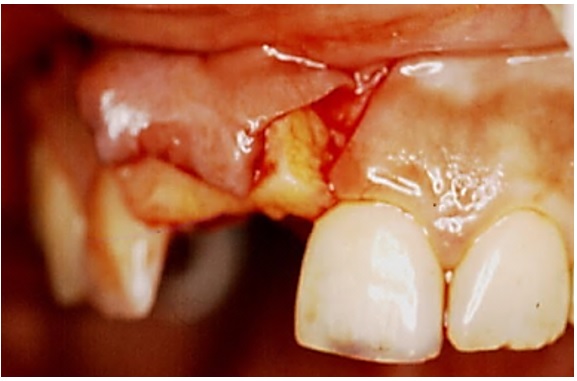

El defecto que presentaba la paciente requirió aumento del grosor más no de la altura del reborde alveolar, por lo que se decidió realizar una técnica de bolsillo (22). El procedimiento quirúrgico consistió en la preparación del receptor mediante una incisión horizontal paracrestal palatina de la zona mesial del 12 a la zona mesial de 21, incluyendo la papila interdental, con incisiones relajantes hechas en ángulo en mesial del 21 y el 12, y elevación de un colgajo mucoso. Luego se tomó un injerto conectivo sin collar de epitelio del sitio donante palatino derecho. Para esto, se realizó una incisión horizontal a 2 mm del margen gingival palatino de mesial del 16 a distal del 13; se elevó la tapa epitelial palatina sin incisiones relajantes. El objetivo de los cortes era poder tomar el injerto de tejido conectivo, los cuales son un corte horizontal interno apical y dos cortes verticales internos mesial y distal. Se procedió a tomar el injerto de tejido conectivo sin collar de epitelio, el cual se dejó dentro del sitio receptor mientras se realizó la sutura del sitio donante palatino (figura 2).

Luego se suturó el injerto dentro del sitio donante y el colgajo se desplazó coronalmente para cubrir la totalidad del injerto (figura 3). Se dieron las instrucciones a la paciente después del procedimiento que incluían: medicación con nimesulida de 100 mg durante 3 días y enjuagues con clorhexidina al 0,12 % durante una semana.